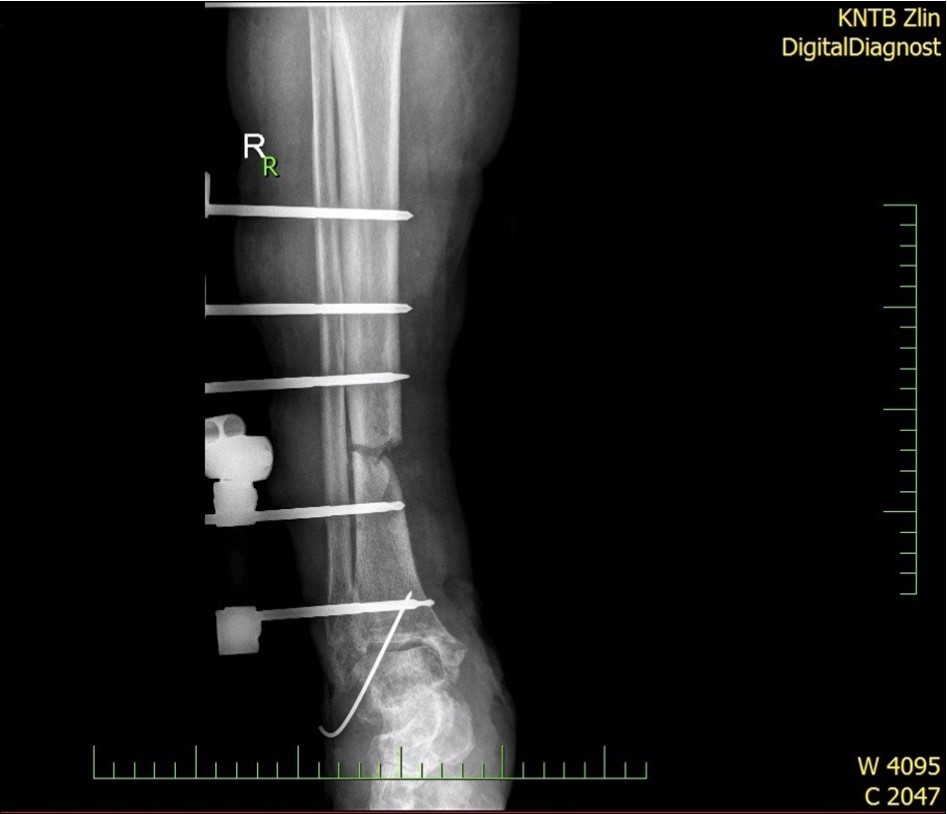

Figure 5.22 January – primary X-ray - Fracture stabilization using external fixator

Figure 6.22 January – primary X-ray - Fracture stabilization using external fixator

Figure 28.23 April. Surgery conversion of osteosynthesis. Removal external fixator and implantation intramedullary tibial nail. Gradual bone healing - last X-ray september 2019

Figure 29.23 April. Surgery conversion of osteosynthesis. Removal external fixator and implantation intramedullary tibial nail. Gradual bone healing - last X-ray september 2019